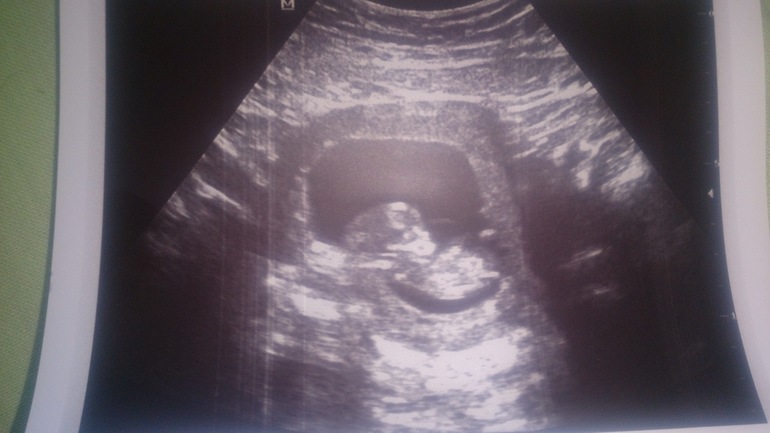

11 неделек и 3 дня

Мы видели нашу совушку , наше солнышко , слышали как бьется сердечко - это незабываемо !! Конечно я разревелась от счастья !😁 Слава Богу Всё хорошо , ничего не выявлено. Малыш уже размером как лайм 😊

Маленькое чудо!узи на 12 неделе мое самое любимое! У вас малыш как будто внутри сердечка)такой формы матка получилась на снимке)